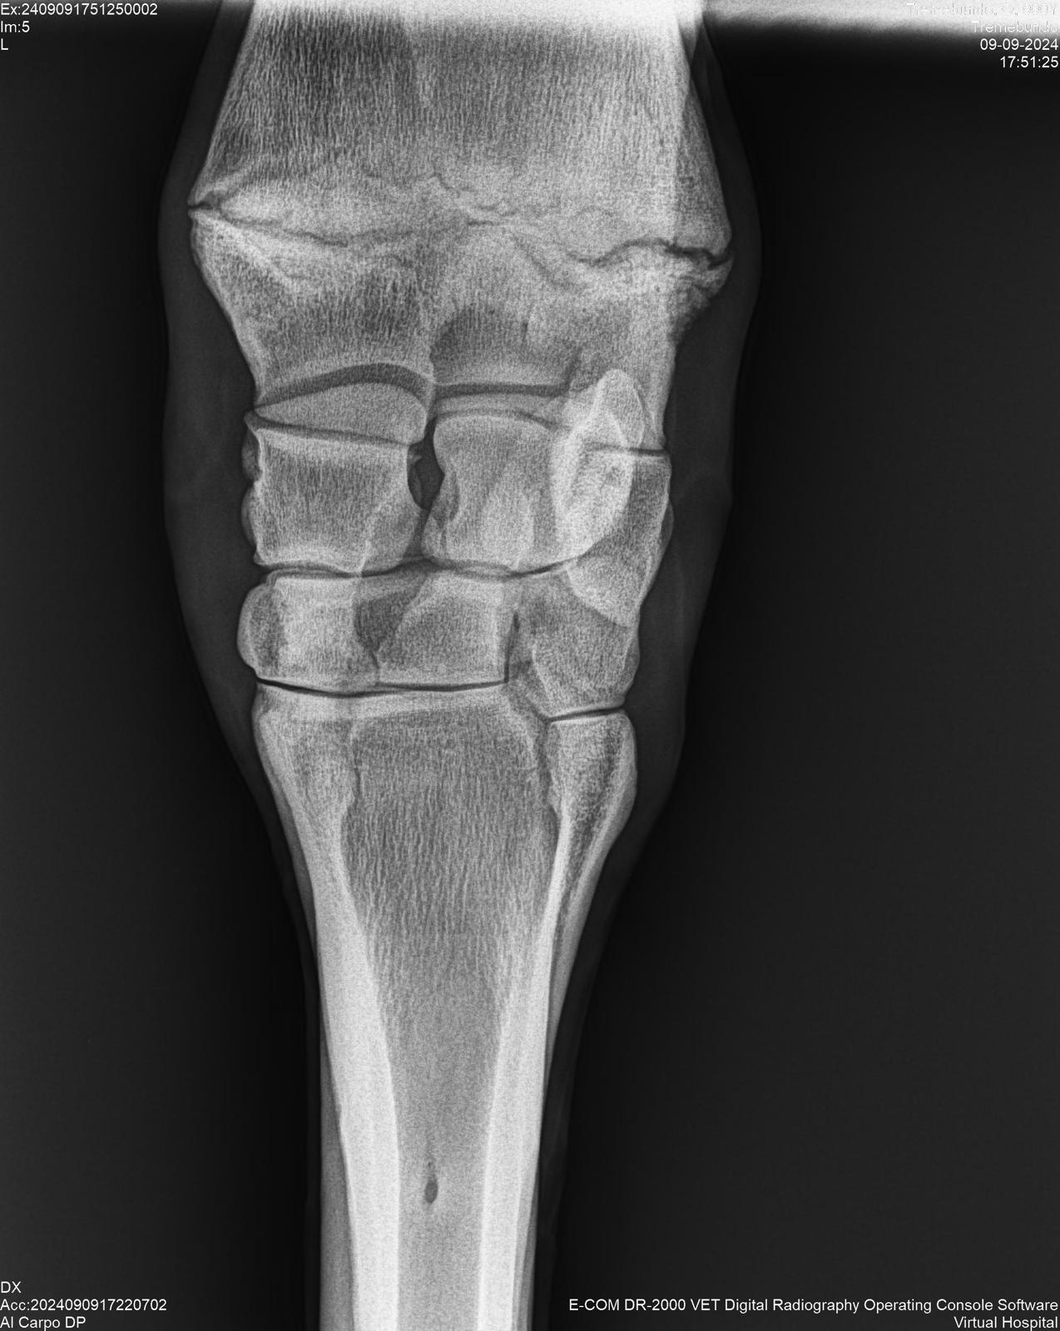

LOTE 37, TREMEBUNDO

Identificador: #291140-

Generacion 2022